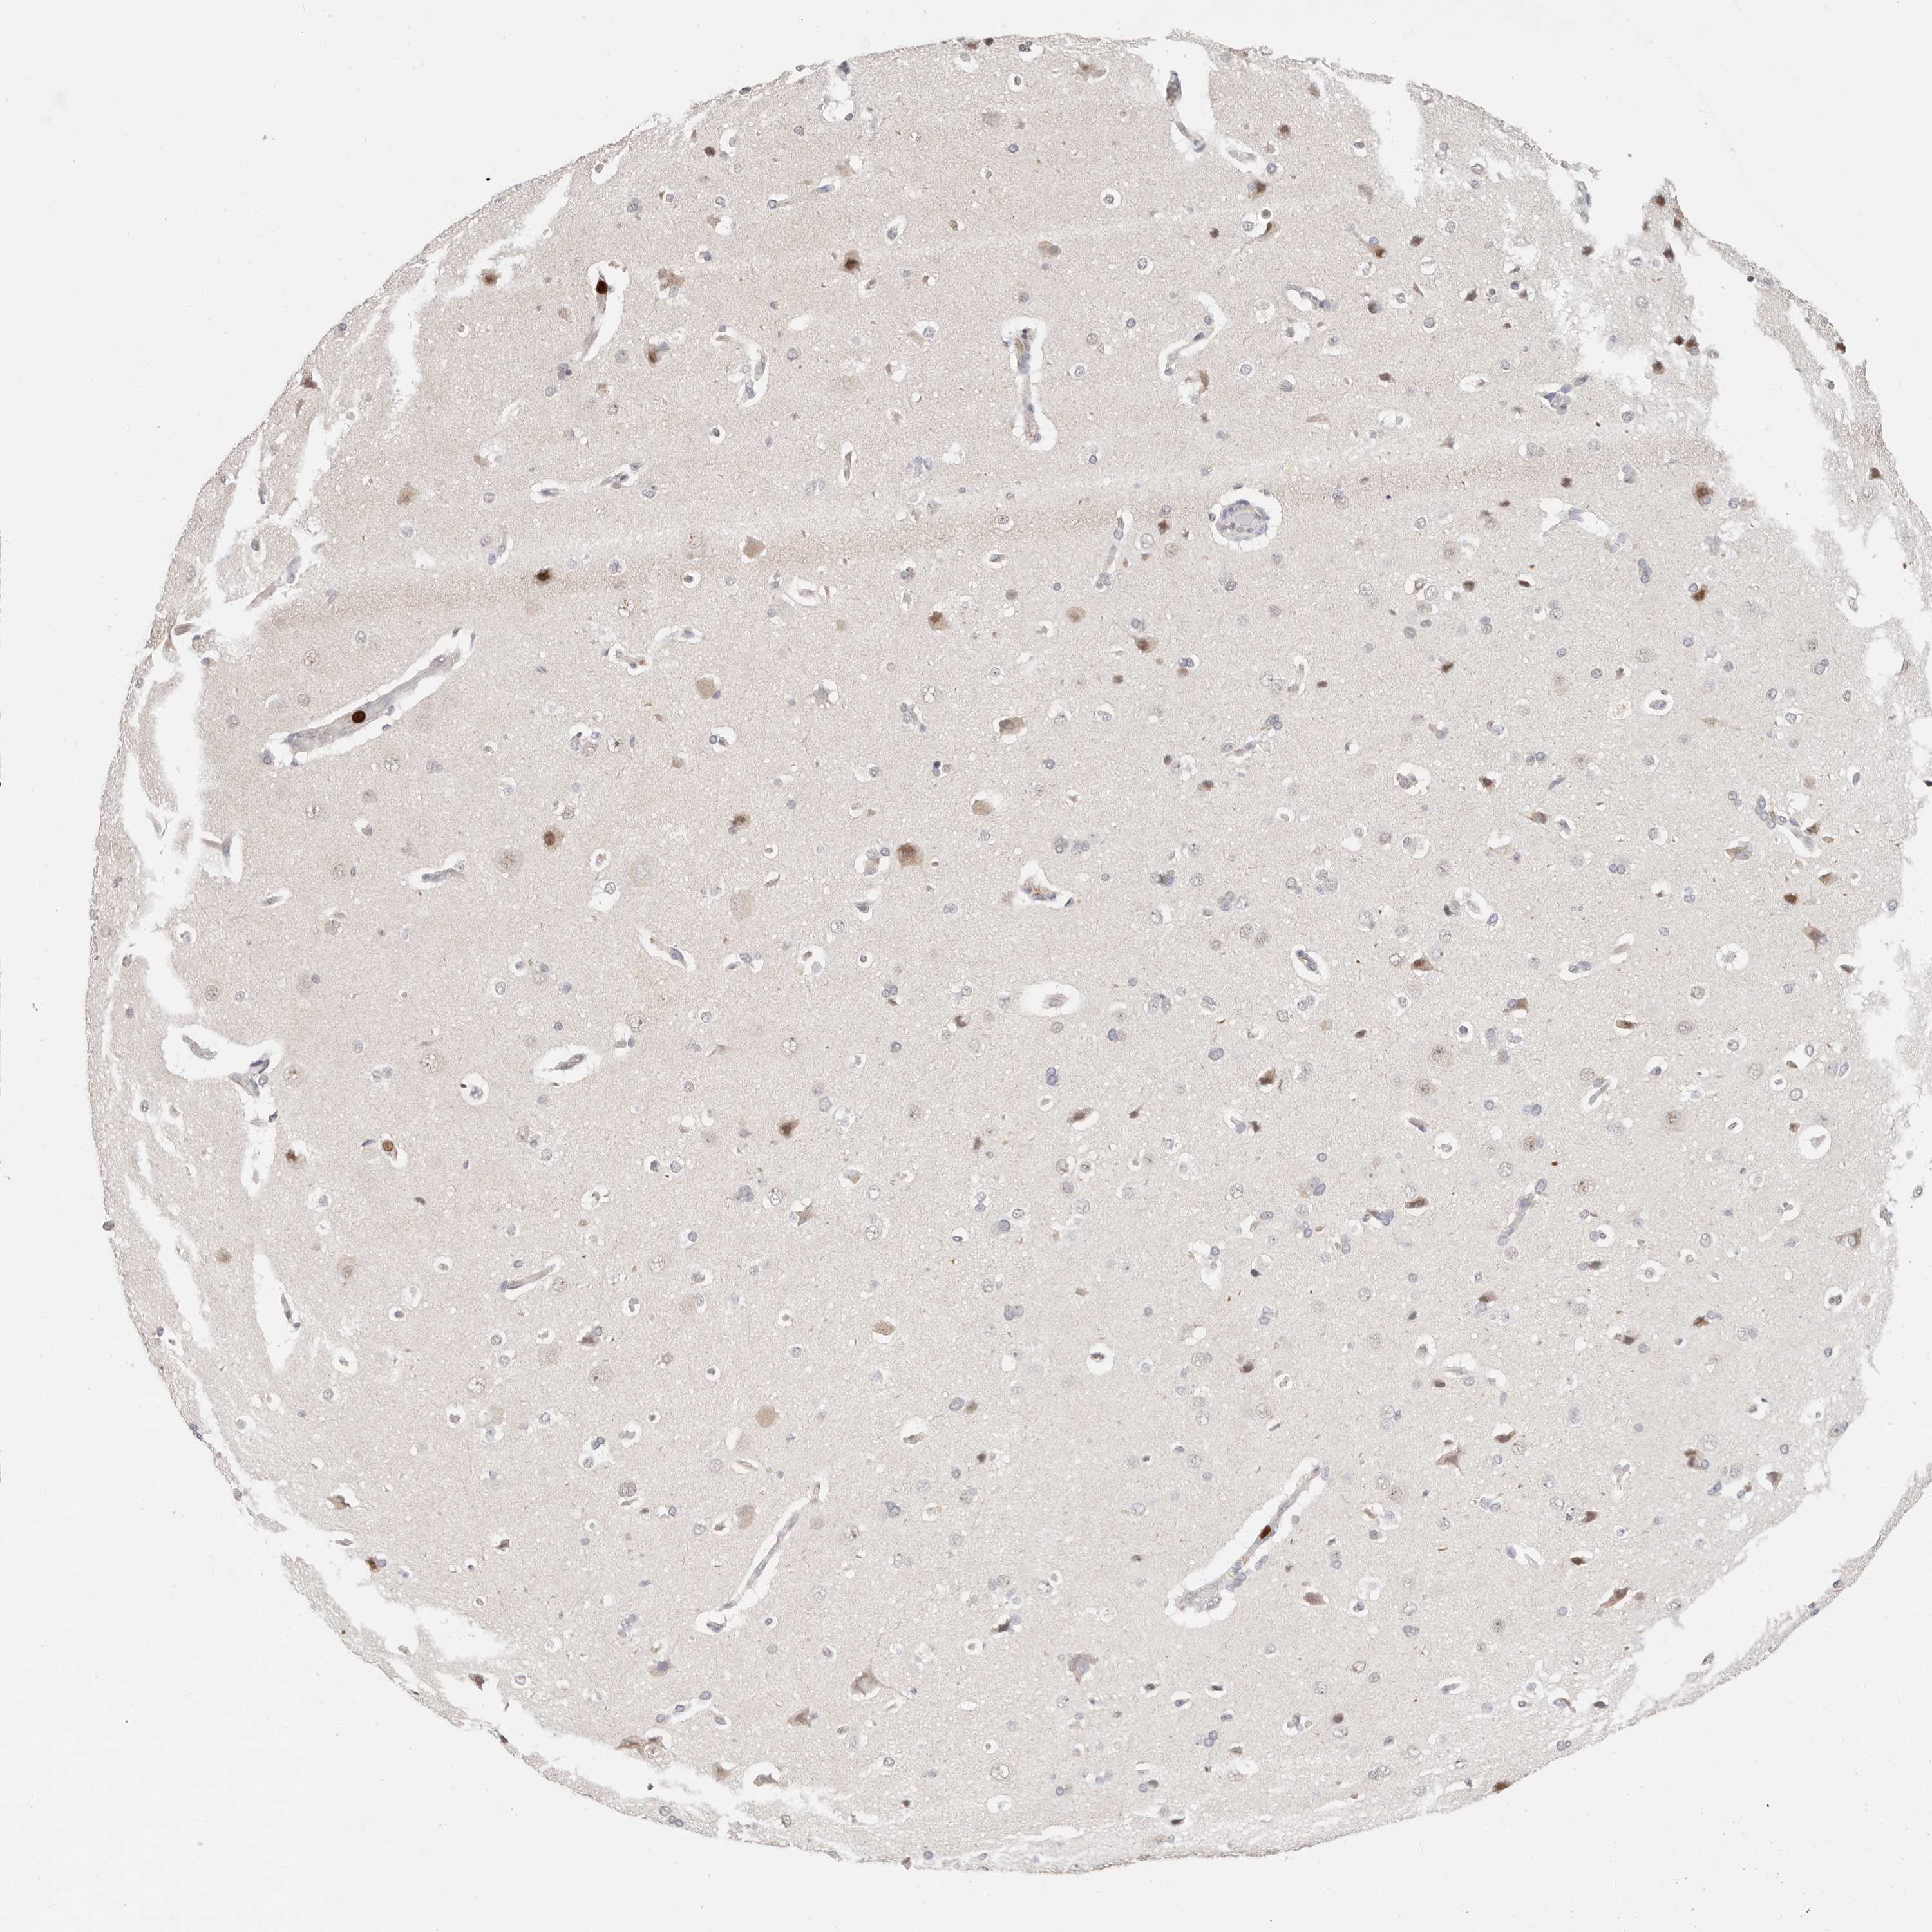

AFDN